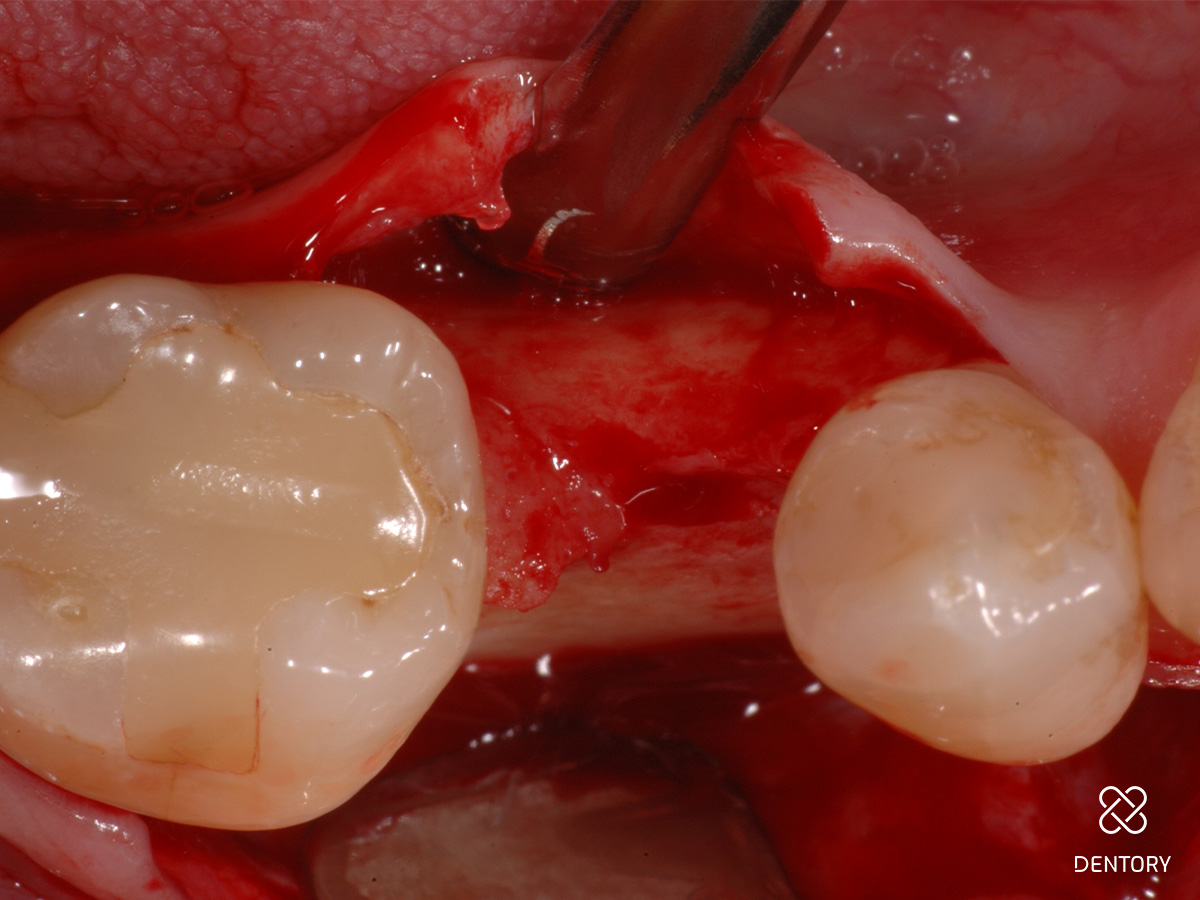

Abbildung 2

Simultane Implantation und GBR: Darstellung des späteren Implantatlagers nach Elevation eines Mukoperiostlappens; es zeigt sich ein horizontal ungenügendes Knochenangebot.